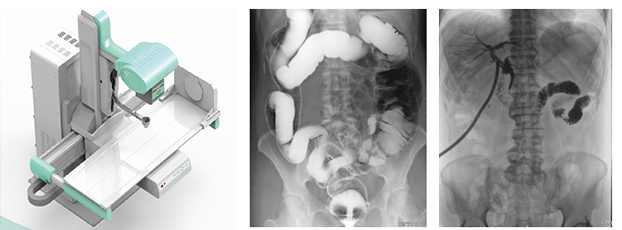

X射線檢查設(shè)備——數(shù)字DR

尤為主要的就是X射線檢查設(shè)備和CT檢查,這兩項(xiàng)檢查確實(shí)是具有相當(dāng)大的輻射性,至少比B超和核磁共振危害大。如X射線檢查設(shè)備,是利用X射線穿透于臟腑內(nèi)并形成影像。X射線是有電離輻射的,且危害性是存在的。一次檢查,輻射量0.02~0.1之間,只要次數(shù)不多,每年只做一次檢查,那么對(duì)機(jī)體的影響是不大的。

CT的輻射和X射線檢查是一樣的,基本并沒(méi)有太大的區(qū)別。主要是檢查的部位,和準(zhǔn)確性不一樣。與X射線檢查設(shè)備相比,CT是一種更為細(xì)致的檢查,它能夠檢查出身體內(nèi)更小的病灶,提升檢查結(jié)果的準(zhǔn)確性。